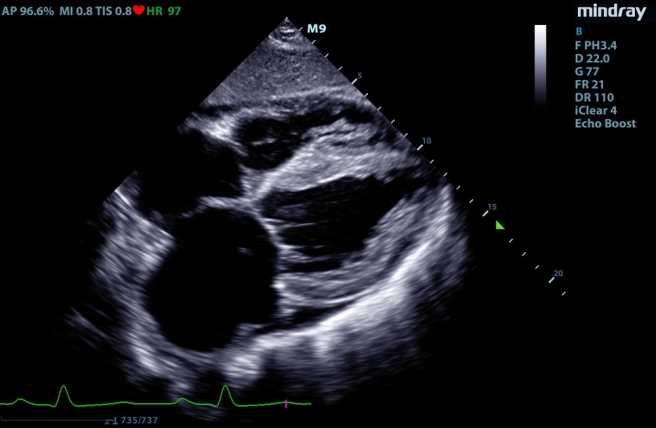

sprzęt Mindray9 używany przez weterynarza kardiologa, Kraków

W badaniach kardiologicznych wykorzystujemy przenośny ultrasonograf klasy PREMIUM – Mindray M-9. Specjalistyczne oprogramowanie i aparat usg zapewniają bardzo dobre obrazowanie, dzięki czemu badanie echo serca jest dokładne i bardzo dobrej jakości.